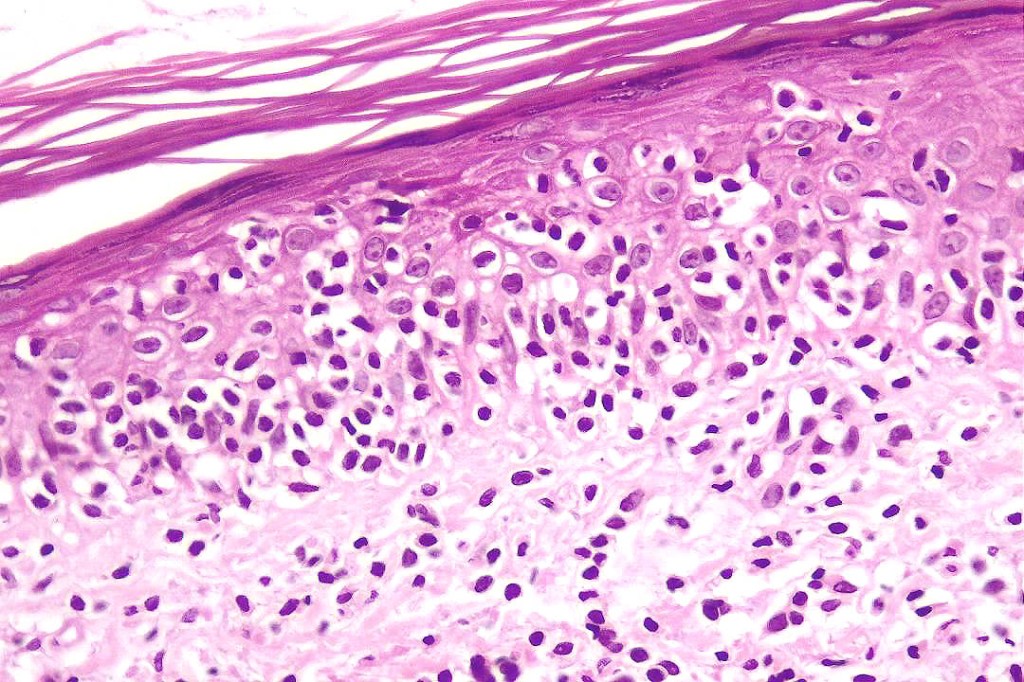

•Hyperkeratosis/parakeratosis

•Acanthosis often psoriasiform

•Very marked epidermotropic infiltrate of atypical lymphocytes including Sézary cells

•Perinuclear halo often present

•Pautrier-like microabscesses